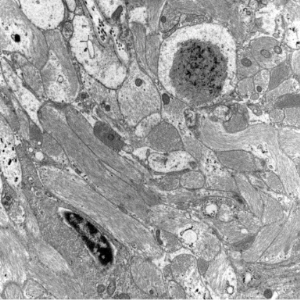

Immunohistochemistry and Ultrastructural Findings

- Lafora body reacts with antibodies against ubiquitin

- KM-279 antibody also reacts with Lafora bodies, corpora amylacea, basophilic masses in the heart, filamentous glycogen inclusions in type IV glycogenosis, and Bielschowsky bodies

- 160kD and 200kD neurofilament, and desmin antibodies also react with Lafora bodies

- still unclear if mutant Laforin is in the Lafora bodies

- polyglucosan bodies - in axons

- Lafora bodies - in neuronal perikarya and dendrites